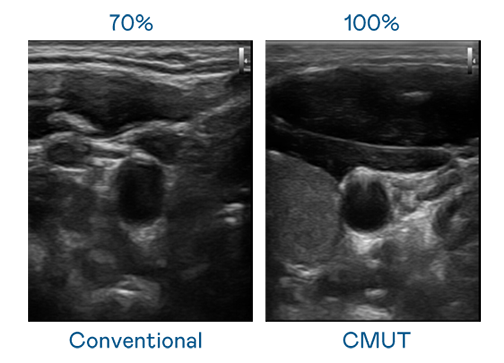

CMUT 技术是一种用电容式微机电元件来产生超音波讯号的技术。与传统 PZT 压电式技术相比,CMUT 频宽增加 30%,更宽频的超音波讯号让影像解析度大幅提升,是实现高影像品质医疗超音波扫描、促进精准医疗发展的关键技术。

大频宽带来超清晰影像

超音波影像的解析度高低,首先取决于探头能发出的讯号频宽。爱游戏 CMUT 可提供高清晰的超音波讯号,提供高频宽、高灵敏度、影像纹理细节更高的超音波影像,协助医护人员缩短影像判读时间及利用精准的医疗影像进行诊断。